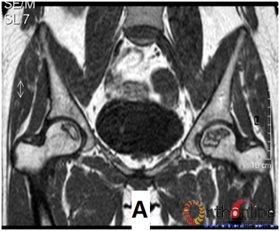

图3 各型坏死打压植骨的结果,(A)Ⅰ型(右侧)和Ⅱ型(左侧)术前MRI显示外侧柱存留;(B)术后7年随访,股骨头维持外形,关节功能好;(C)Ⅲ型(双侧)术前MRI显示外侧柱破坏;(D)术后5年,右侧股骨头维持外形,左侧塌陷

Fig 3 The results of different osteonecrotic type by impacting bone graft,(A)Type Ⅰ(right),type Ⅱ(left) MRI showed the preservation of the lateral pillar preoperatively; (B) Seven years after operation, the femoral head still maintain sphere, hip function is excellent; (C) Type Ⅲ (both side) MRI showed the involved of lateral pillar by necrosis; (D)Five years after operation, the femoral head still maintain sphere in right side, collapse occurred in left side.